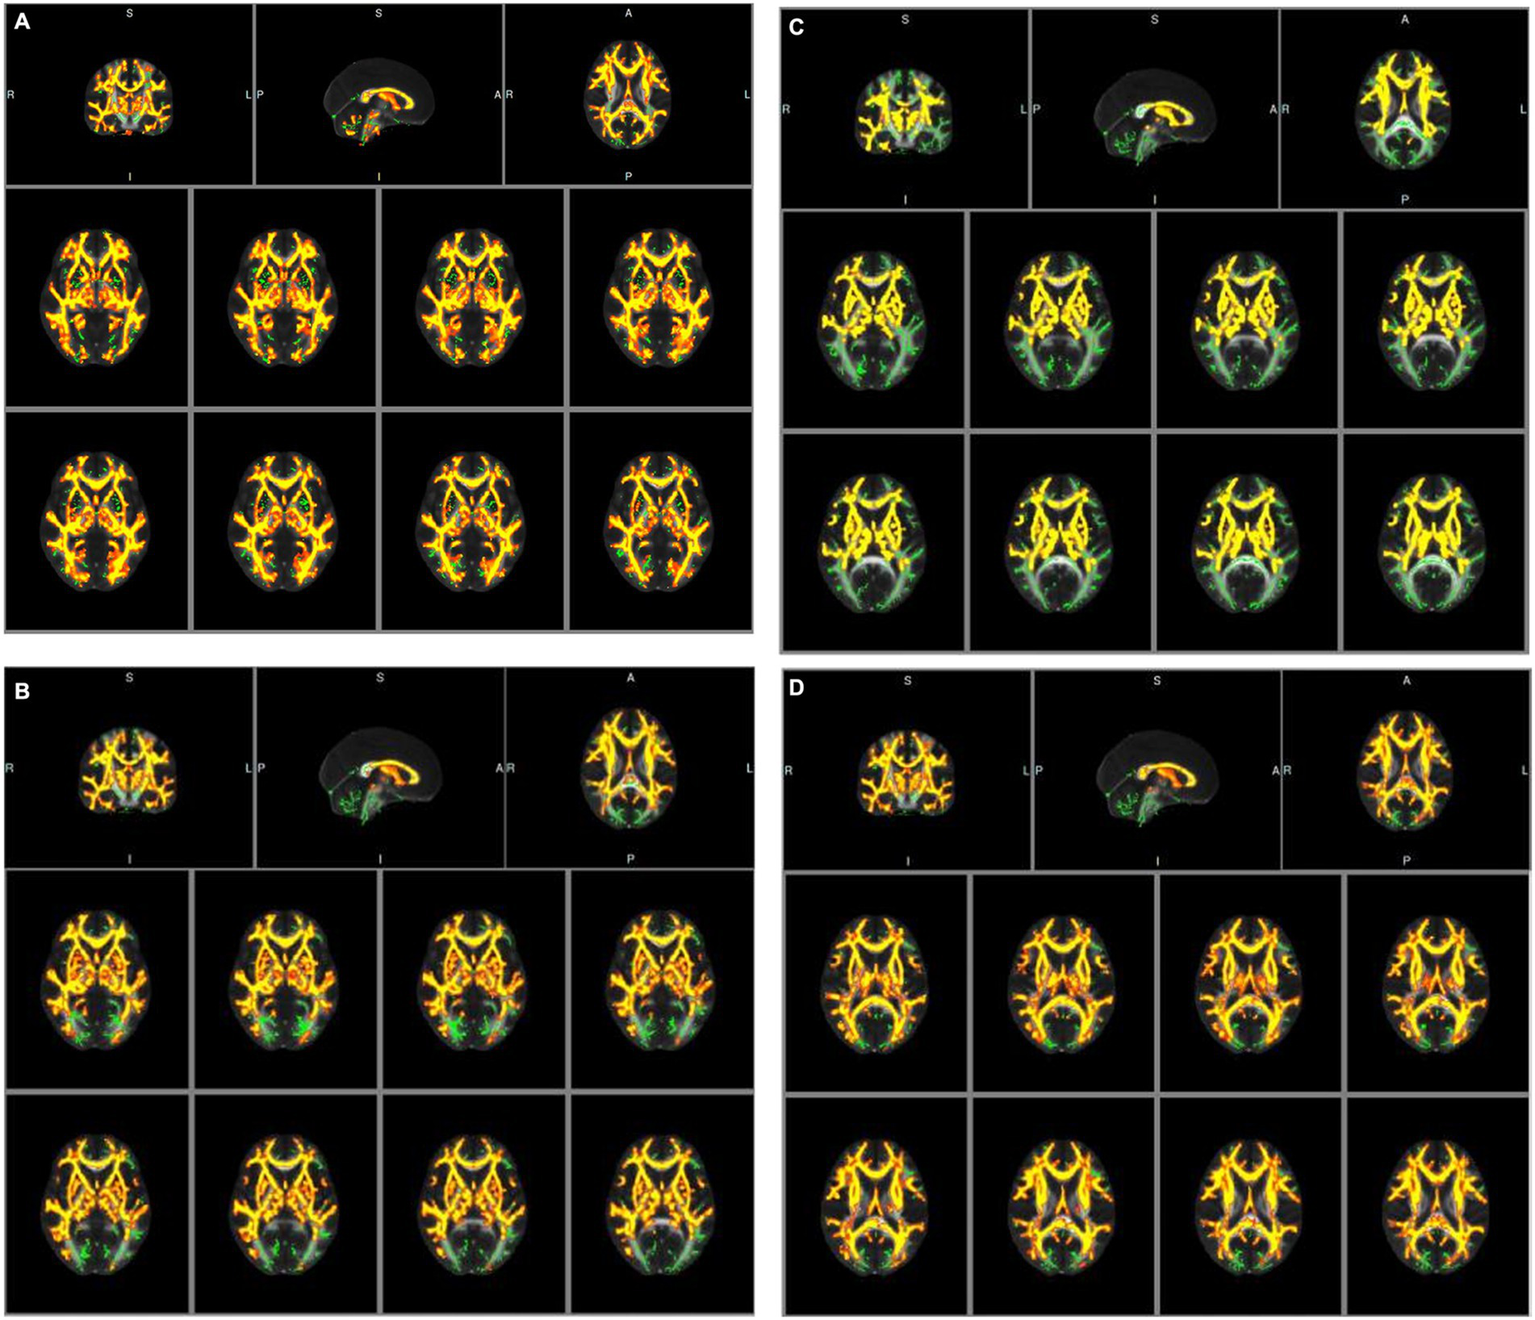

An analysis of baseline data, including age, gender, vascular risk factors, laboratory testing data, and treatment history, for participants undergoing diffusion tensor imaging (DTI) examination revealed no statistically significant differences (p > 0.05). However, tract-based spatial statistics (TBSS) analysis identified significant differences in all diffusion indicators between the groups. Specifically, in patients with congestive heart failure (CHF) and left ventricular ejection fraction (LVEF) < 50%, fractional anisotropy (FA) decreased significantly, whereas mean diffusivity (MD), axial diffusivity (AD), and radial diffusivity (RD) increased significantly, compared to CHF patients with LVEF≥50% (see Tables 5a–d; Figures 2A–D).

Figure 2

(A) Tract-based spatial statistic results of fractional anisotropy (FA) images between the two groups of CHF patients. Green represents mean skeleton of all participants; red and yellow represents regions with decreased FA in CHF patients with LVEF<50% (p < 0.05, TFCE corrected for multiple comparisons). (B) Tract-based spatial statistic results of mean diffusivity (MD) images between the two groups of CHF patients. Green represents mean skeleton of all participants; red and yellow represents regions with increased MD in CHF patients with LVEF<50% (p < 0.05, TFCE corrected for multiple comparisons). (C) Tract-based spatial statistic results of axial diffusivity (AD) images between the two groups of CHF patients. Green represents mean skeleton of all participants; red and yellow represents regions with increased AD in CHF patients with LVEF<50% (p < 0.05, TFCE corrected for multiple comparisons). (D) Tract-based spatial statistic results of radial diffusivity (RD) images between the two groups of CHF patients. Green represents mean skeleton of all participants; red and yellow represents regions with increased RD in CHF patients with LVEF<50% (p < 0.05, TFCE corrected for multiple comparisons).

Compared to CHF patients with LVEF≥50%, FA decreased significantly while MD, AD and RD increased significantly in CHF patients with LVEF <50% in our study. The FA value represents the degree of anisotropy of water molecule dispersion and measures the ability of water molecules to diffuse directionally in tissues, with a variation range of 0–1, and is an indicator of white matter integrity in the brain (33). Loss of myelin in white matter fibers, damage to axonal cell membrane integrity, and axonal transport speed all affect FA values (34). The decrease in FA value indicates that the brain white matter fiber structure of CHF patients with LVEF <50% has been damaged, resulting in a decrease in the anisotropy of water molecule dispersion. The MD value represents the overall diffusion size and is independent of the diffusion direction. The lower the MD value, the more limited the tissue structure (34). We observed a significant increase in MD in CHF patients with LVEF<50%, possibly due to an increase in free water molecules and expansion of the intercellular space leading to changes in the diffusion rate of water molecules. The AD value and RD value represent the degree of diffusion of water molecules parallel and perpendicular to the direction of fiber bundle movement, respectively. The increase in AD value is related to axonal damage, while the increase in RD value is related to demyelination (35, 36). Therefore, the above four diffusion index abnormalities indicate more significant changes in the microstructure of the brain white matter fiber bundles in the CHF patients with LVEF<50%, which are difficult to detect in traditional MRI sequences.

In our study, the brain regions with statistically significant changes in white matter fiber tracts included anterior thalamic radiation, corticospinal tract, cingulum (cingulate gyrus), cingulum (hippocampus), forceps major, forceps minor, inferior fronto-occipital fasciculus, inferior longitudinal fasciculus, superior longitudinal fasciculus, uncinate fasciculus and superior longitudinal fasciculus (temporal part). In previous studies, in cognitive impairment caused by CSVD, the damaged WM was mainly located in the prefrontal pathways of the thalamus and caudate lobe (e.g., anterior thalamic radiation, forceps minor, inferior fronto-occipital fasciculus, inferior longitudinal fasciculus, superior longitudinal fasciculus), which are significantly correlated with executive and attention functions (37). The forceps minor and forceps major are the main parts that make up the corpus callosum, which mainly transmit information in both hemispheres of the brain. The forceps minor connects the prefrontal cortex of both hemispheres and plays an important role in executive function (38); the forceps major connects the bilateral parietal cortex, and its integrity is related to visuospatial function and working memory (39). In the frontal lobe, fasciculus, which connects the orbital frontal cortex and plays an important role in attaching emotions to visuospatial function (40). Studies suggest that the human cingulum bundles are correlate with attention, memory, and executive function, including some of the most relevant cingulum connections, such as cingulate gyrus and hippocampus, which are even related to emotions (41). The projective fibers interconnect the cortical and subcortical structures, therefore in our study, a similar trend was also observed in the corticospinal tract. The above-mentioned lesions of the white matter fiber bundles involving the cortex, default network, limbic system, pyramidal tract, and other central nervous systems provide a pathophysiological basis for impaired cognitive function in CHF patients with decreased LVEF.